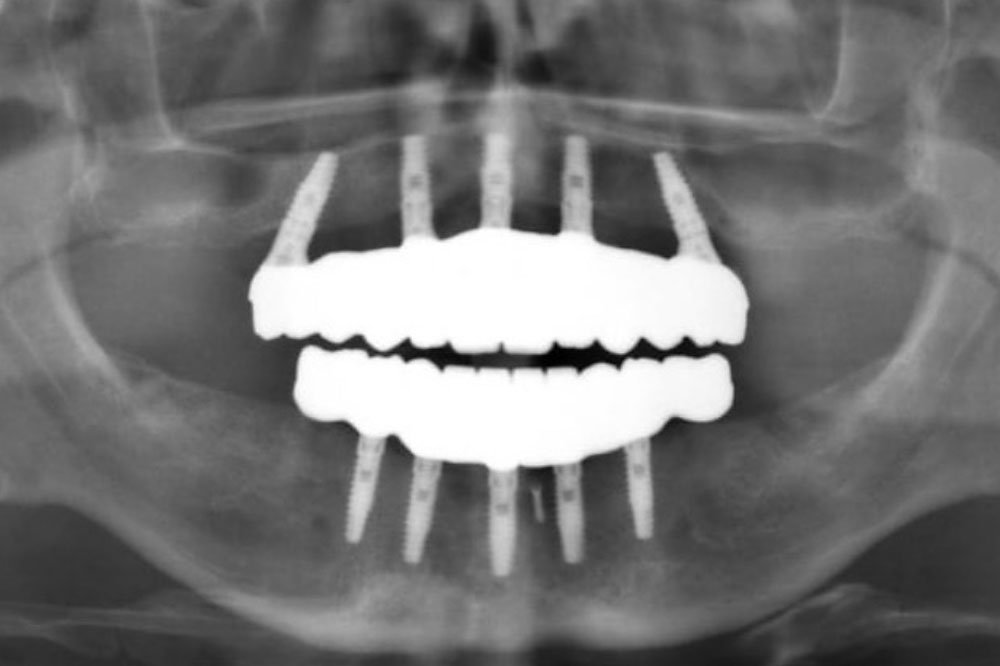

Implant Prosthetics: Full Arch Restorations

- Full arch restorative protocols and guidelines

- Step-by-step to predictable full arch aesthetics and long term stability

- Fixed implant full arch techniques and materials

- Master Fixed Implant Full Arch Techniques

- Gain expertise in fixed implant-supported full arch restorations, including the latest materials and techniques for creating stable, durable, and esthetically pleasing

- Learn how to design fixed prostheses that integrate seamlessly with implants and provide long-term functional and aesthetic